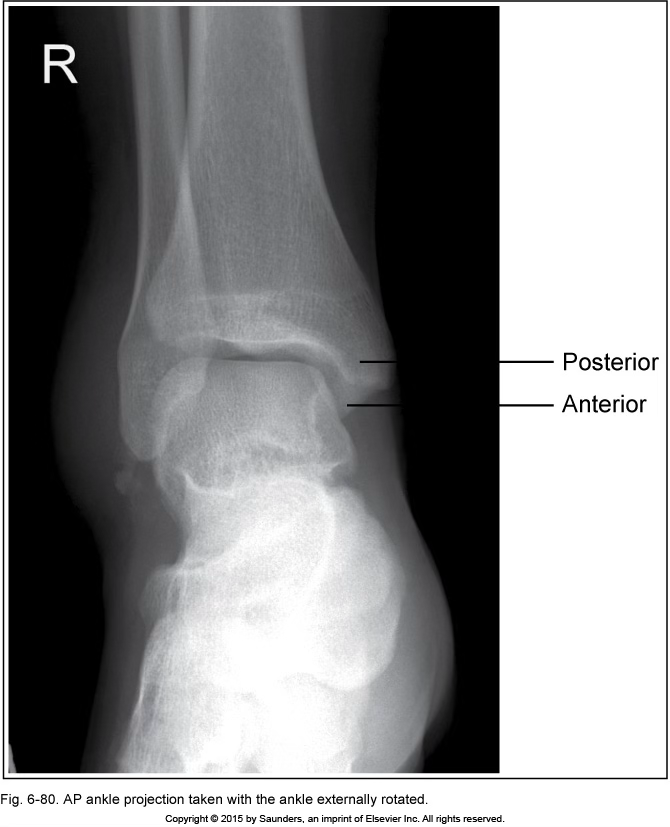

AP ankle

accurate positioning

ankle externally rotated

tibia superimposing fibula